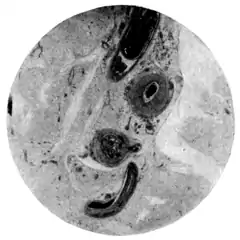

|style="padding-right:1em;"|Fig. 1.—Schistosomum japonicim in vessels of mesentery.

(Microphotograph: Dr. Henderson.) ||Fig. 2.—Eggs of Schistosomum japonicim embedded in walls